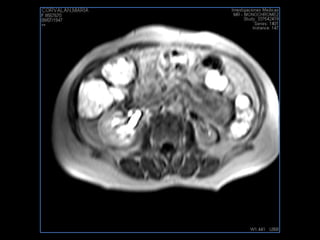

PROTOCOLO pancreas/ riñon AXIAL fat sat /AX in phase out phase AX T1 +SAG T2  COR T2, CON   GADOLINIO :  COR T1+AX T1(DIN) SAT: NO  FASE: RL THK: 4MM  COIL:  GAP: (FACTOR 1.4) 1MM FOV: 40 CM NEX:2 SINCRONIZACION RESPIRATORIA EN 3 O 4 CICLOS ALE